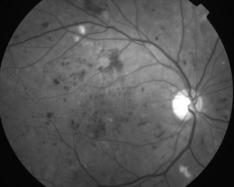

RETINOPATHIE DIABETIQUE NON PROLIFERANTE SEVERE

IMG0004.JPG